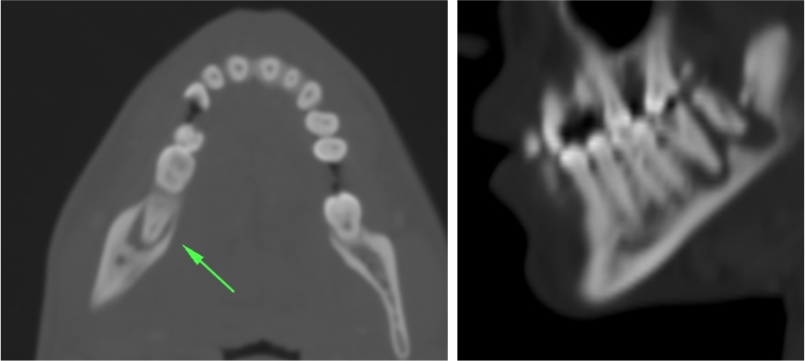

ESPACIO MASTICADOR:

En este espacio encontraremos los músculos de la masticación y el hueso de la mandíbula con las piezas dentarias. Por tanto, en esta localización encontraremos infecciones de origen dentario que cursan con aumento de volumen, dolor, calor y rubor facial y que pueden acompañarse de disfagia y disfonía. Cuando se originan en el 2º y 3º molar pueden extenderse al espacio submandibular mientras que los que se presentan en los dientes más anteriores tienden a difundir al espacio sublingual.

Hallazgos:

- Aumento de partes blandas y afectación de la grasa adyacente a los músculos de la masticación (celulitis y miositis).

- En las ventanas óseas, dehiscencia de la cortical del hueso de la cara mandibular dental de la pieza comprometida, estas áreas estarán en relación con colecciones líquidas hipoatenuadas con un realce en anillo de sus rebordes, visibles en las ventanas de partes blandas.

- Es muy importante identificar signos de osteomielitis mandibular:

- Osteopenia.

- Engrosamiento del periostio (periostitis), reacción perióstica (triángulo de Codman)

- Lisis o ruptura cortical.

- Hipondensidad, Pérdida de hueso trabecular

- Eclerosis periférica

- Gas.

Es importante recordar que el espacio masticador se extiende por la cara, la parte lateral de cabeza superando el arco zigomático e incluye al músculo temporal que se inserta en el hueso parietal, por lo que es importante incluirlo en nuestra valoración.

ENFERMEDAD DENTAL.

Ante pacientes con hinchazon facial, se debe sospechar enfermedad endodontal.

Puede ser identificada mediante TC por el estudio de las racies dentales, las cuales presentarán una lucencia o baja densidad que las rodea = signo de las raíces flotantes = afectación endodental = caries bacteriana que pogresa, afecta la pulpa y finalmente dañan la raíz del diente y el hueso de alrededor produciendo una osteomielitis localizada y abscesos subperiósticos o colecciones que se desplazan a tejidos superficiales.